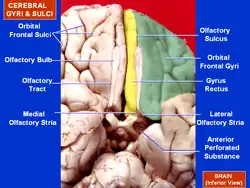

Olfactory tract lying in olfactory sulcus and olfactory striae labelled | |

The olfactory tract and olfactory bulb lie in the olfactory sulcus[1] a sulcus formed by the medial orbital gyrus on the inferior surface of each frontal lobe. The olfactory tracts lie in the sulci which run closely parallel to the midline. Fibers of the olfactory tract appear to end in the antero-lateral part of the olfactory tubercle, the dorsal and external parts of the anterior olfactory nucleus, the frontal and temporal parts of the prepyriform area, the cortico-medial group of amygdala nuclei and the nucleus of the stria terminalis.[2]

The olfactory tract divides posteriorly into a medial and a lateral stria.[1] Caudal to this is the olfactory trigone, and the anterior perforated substance.[1]

Lateral olfactory stria

Plan of olfactory neurons. Orbital surface of frontal lobe olfactory sulcus shown in red.

Orbital surface of frontal lobe olfactory sulcus shown in red.